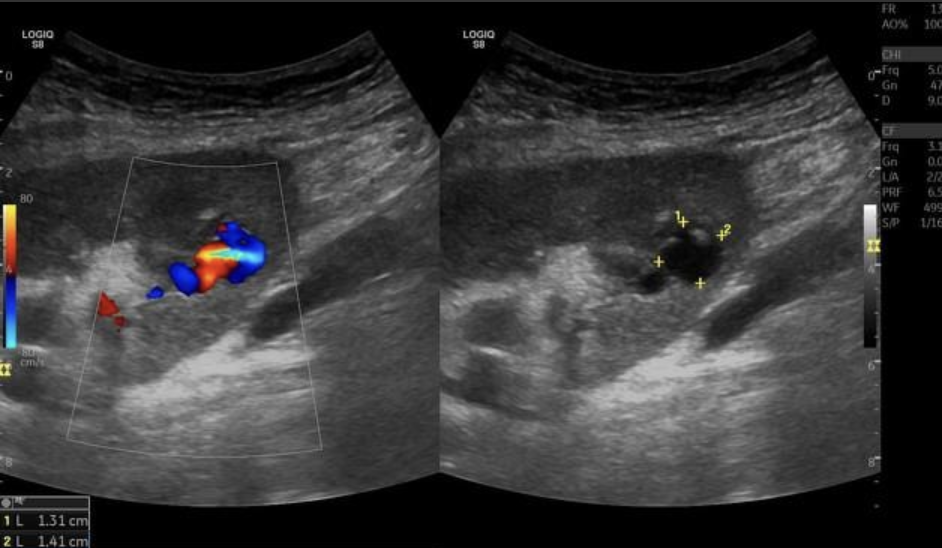

AVF (Arteriovenous Fistula) → abnormal connection between artery and vein in kidney

clinical hx: congenital, iatrogenic, spontaneous

s/sx: hematuria, flank pain, abdominal bruit

2D US: cystic space

color doppler: focal aliasing

DDX: aneurysm

Renal Artery Aneurysm → focal dilation of renal artery

clinical hx: congenital, inflammatory disease

s/sx: asymptomatic

2D US: cystic mass medial to renal hilum, connection to main artery

color doppler: helical flow

DDX: AVF